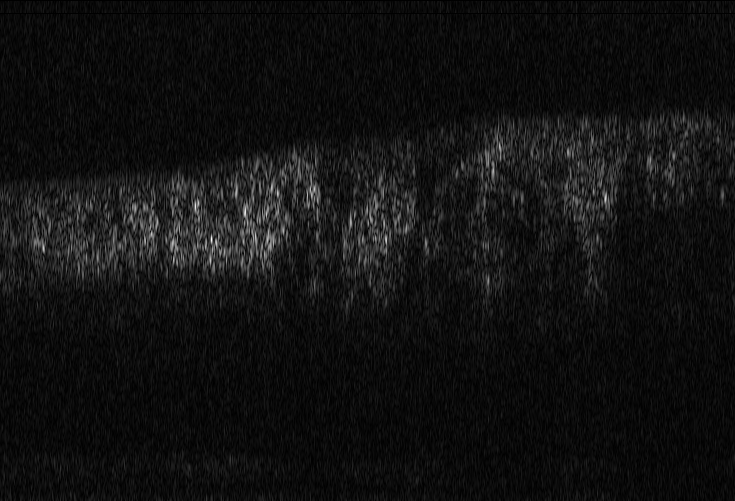

(a) Reference

(b) (25.20, 0.55, 0.04)

Refer to caption

(c) (26.49, 0.66, 0.03)

(d) (27.78, 0.70, 0.06)

Figure 10: OCT reference reconstruction (a) and reconstructions with sub-optimal parameters (b)-(d) leading to geometric deviations (b)-(c) and low resolution (d). Here, (d) is wrongly judged as best reconstruction by PSNR and SSIM, LPIPS is able to ignore the small spatial deviations.

Good dispersion compensation should provide images with a depth resolution that is optimized for the system at hand. In the ophthalmic application of AO-OCT, this high axial resolution allows for the visualization and identification of the different retinal layers (citep \@BBN(Shirazi et al., 2020; Brunner et al., 2021; Wojtkowski et al., 2004)), different retinal layers and structures, such as blood vessels. In the first example Figure 9 the clear separation of the different layers in the posterior retina, such as the photoreceptor bands and the retinal pigment epithelium, is crucial for clinicians/researchers who investigate the structure and function of the healthy and the diseased human retina (citep \@BBN(Jonnal et al., 2014)). Therefore, in this example, the reconstruction shown in Figure 2 (d) should have clearly been rated the lowest as the axial resolution is the lowest because of faulty dispersion compensation, which cannot be fixed by further post-processing. In the second example Figure 10, a cross-sectional view of three retinal vessels which are embedded in the nerve fibre layer is given. Changes in the thickness of vessel walls are an important early biomarker for retinal diseases such as diabetic retinopathy, cf. (citep \@BBN(Bakker et al., 2022)). Again, the reconstruction with faulty dispersion compensation shown in Figure 10(d) should have been rated the lowest. The loss in axial resolution worsens the visualisation of the vessel walls and would lead to inaccurate measurements of the vessel wall thickness. In the current version of the algorithm the parameters which determine the amount of dispersion, rotation and curvature compensation applied by the reconstruction algorithm have to be set manually. Therefore, automated evaluation would be very helpful to fasten the process. The standard metrics are not suitable here, as PSNR and SSIM wrongly assess that reconstruction as the best, and, as expected, penalize harder the geometric deviations in (b) and (c). The geometric deviations are not beneficial, but could be fixed by post-processing unlike image (d).